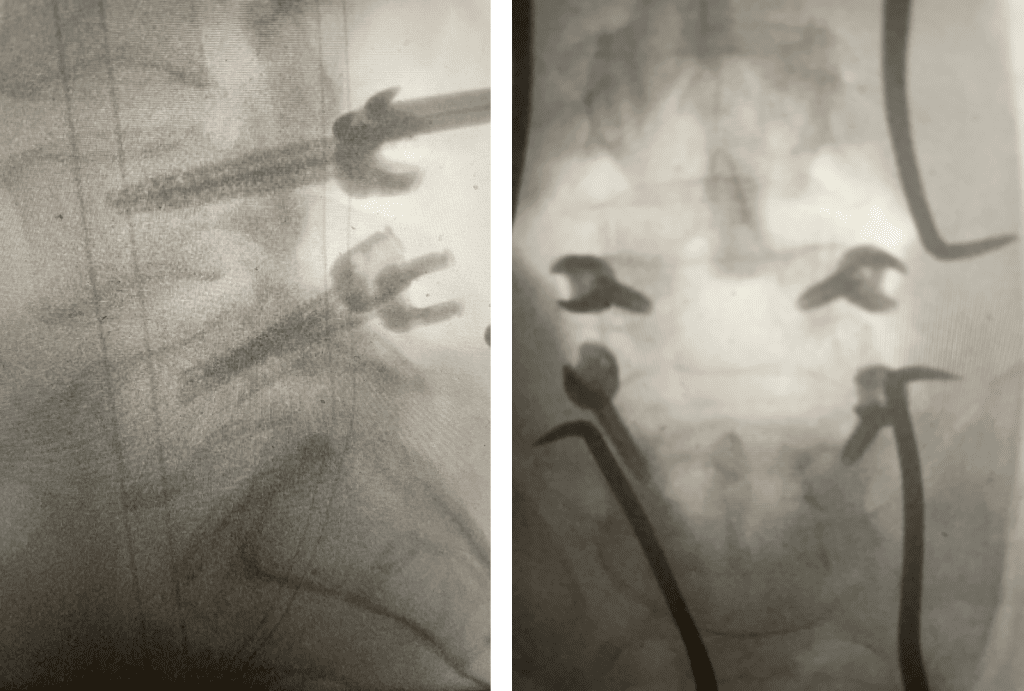

Fig 3: Intraoperative lumbar fluoroscopic lateral and AP images demonstrating good screw placement in performing an L4-5 fusion.

During the surgery we encountered the “cyst” as it was coming from inside or medial joint space between the two bony processes that make up the facet joint itself, like two puzzle pieces that fit together with a synovial-lined space that can for a degenerative synovial cyst. The cyst is like a pimple and actually is quite satisfying to pop and release the material that looks like curd as it is rarely liquid. Because of the consistency and the location, they are not really able to be aspirated or found. After we did what we set out to do which was to make the nerve sac without any pressure as well as the L5 nerve roots, which are most affected at this level. We performed a fusion with two titanium screws in L4 and two in L5, which were connected by rods that were bent or lordosed (Fig 3). They are easy to put in and serve the purpose of connecting the two levels to prevent any relative motion or translation of L4 on L5. This also most importantly prevents the body from signaling the spine to make arthritis to attempt to auto stabilize itself. After the surgery the patient had relief of his right leg pain and had an uneventful postoperative course.